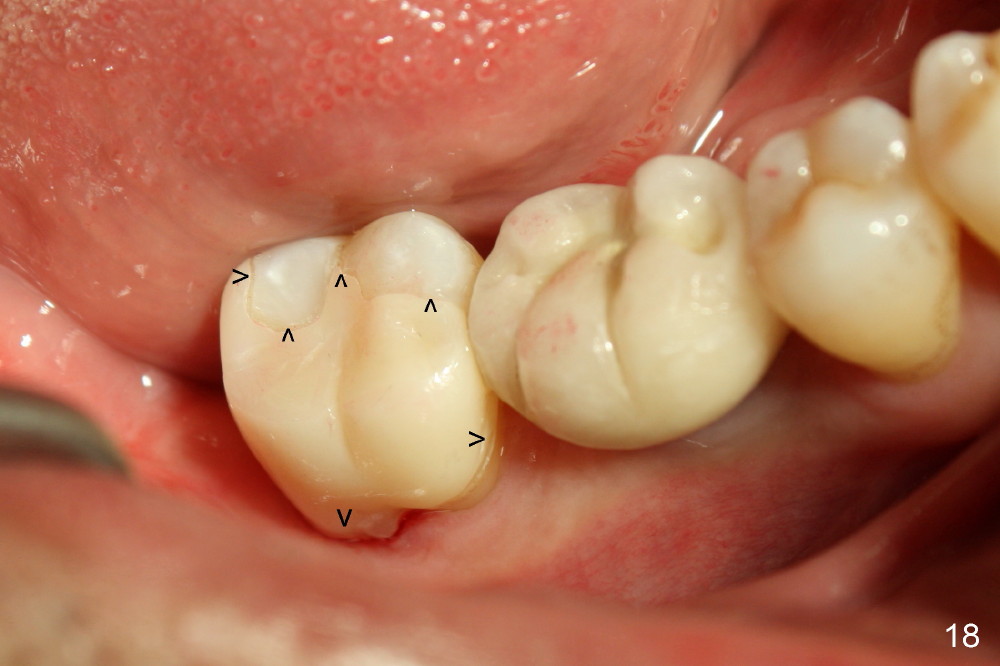

While the bone continues growing around the implant 1.5 years postop (Fig.17, as compared to Fig.12), the tooth #31 loses composite distally (*). A Zirconia onlay is cemented 1 year 10 months post implantation (Fig.18 arrowheads); the posterior interdigitation remains normal (Fig.19).